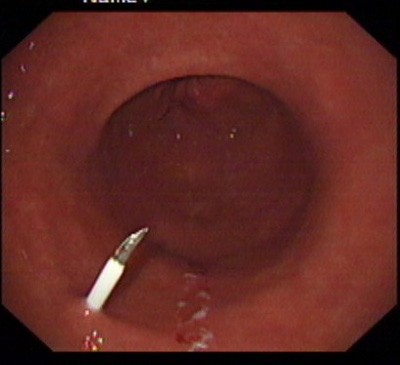

在消化科董蕾主任关心和指导下,消化科王进海教授,张利医师成功地给一位脑出血后吞咽困难的患者实施了经皮内镜下胃造瘘术。

该患者系男性,76岁,脑出血后留有吞咽困难后遗症,不能自主进食,需长期留置胃管供给营养,严重的影响了病人的生活质量和原发病的恢复。经皮内镜下胃造瘘术(Percutaneous endoscpic gastrostomy,PEG)是一种无需常规外科手术和全身麻醉的造瘘技术,可以在胃镜室或病房局麻下进行,因此是一种操作简便、创伤小、安全可靠的方法。该例患者在胃镜室局麻下进行手术,手术过程约10分钟,术后病人无明显不适,3天后即可从造瘘管给食物并出院。